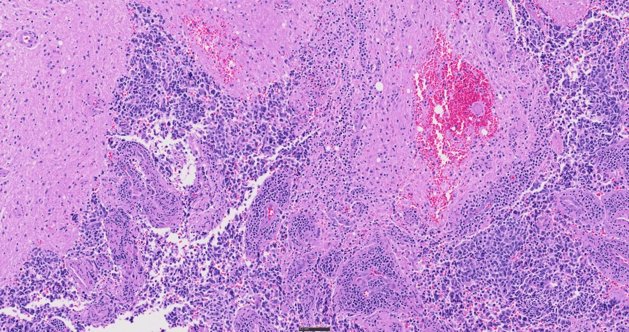

H&E染色组织,40X

SLIDEVIEW VS200系统最多支持六个高性能X Line物镜,采用真彩LED照明,配备色彩经过校正的相机配置文件,可提供清晰的全玻片图像。扫描仪经过精心设计,可稳定再现样品和染色特征,不仅大幅减少了重新扫描的需要,还支持高效诊断。

通过五种成像模式——明场、偏光、荧光、暗场和相衬——发现样品中的更多细节,还可在单次扫描中结合使用多种技术,进行更全面的观察。这种灵活性为观察组织学和细胞学样品提供了广泛的应用可能性,涵盖了从常规病理学到癌组织的复杂分子表征等应用。